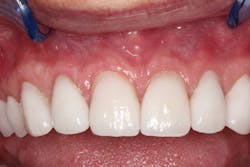

Chris returned for us to cement the crowns. The lab had fabricated exquisite-looking crowns that function properly (figures 7–9). We prepped the uppers in one day, lowers in another day, and cemented all in one day.

Figure 7: Final crowns

Figure 8: Final crowns

Figure 9: Final crowns

I checked for fit and fine-tuned the patient’s bite with T-Scan (Tekscan), and Chris has been smiling ever since.